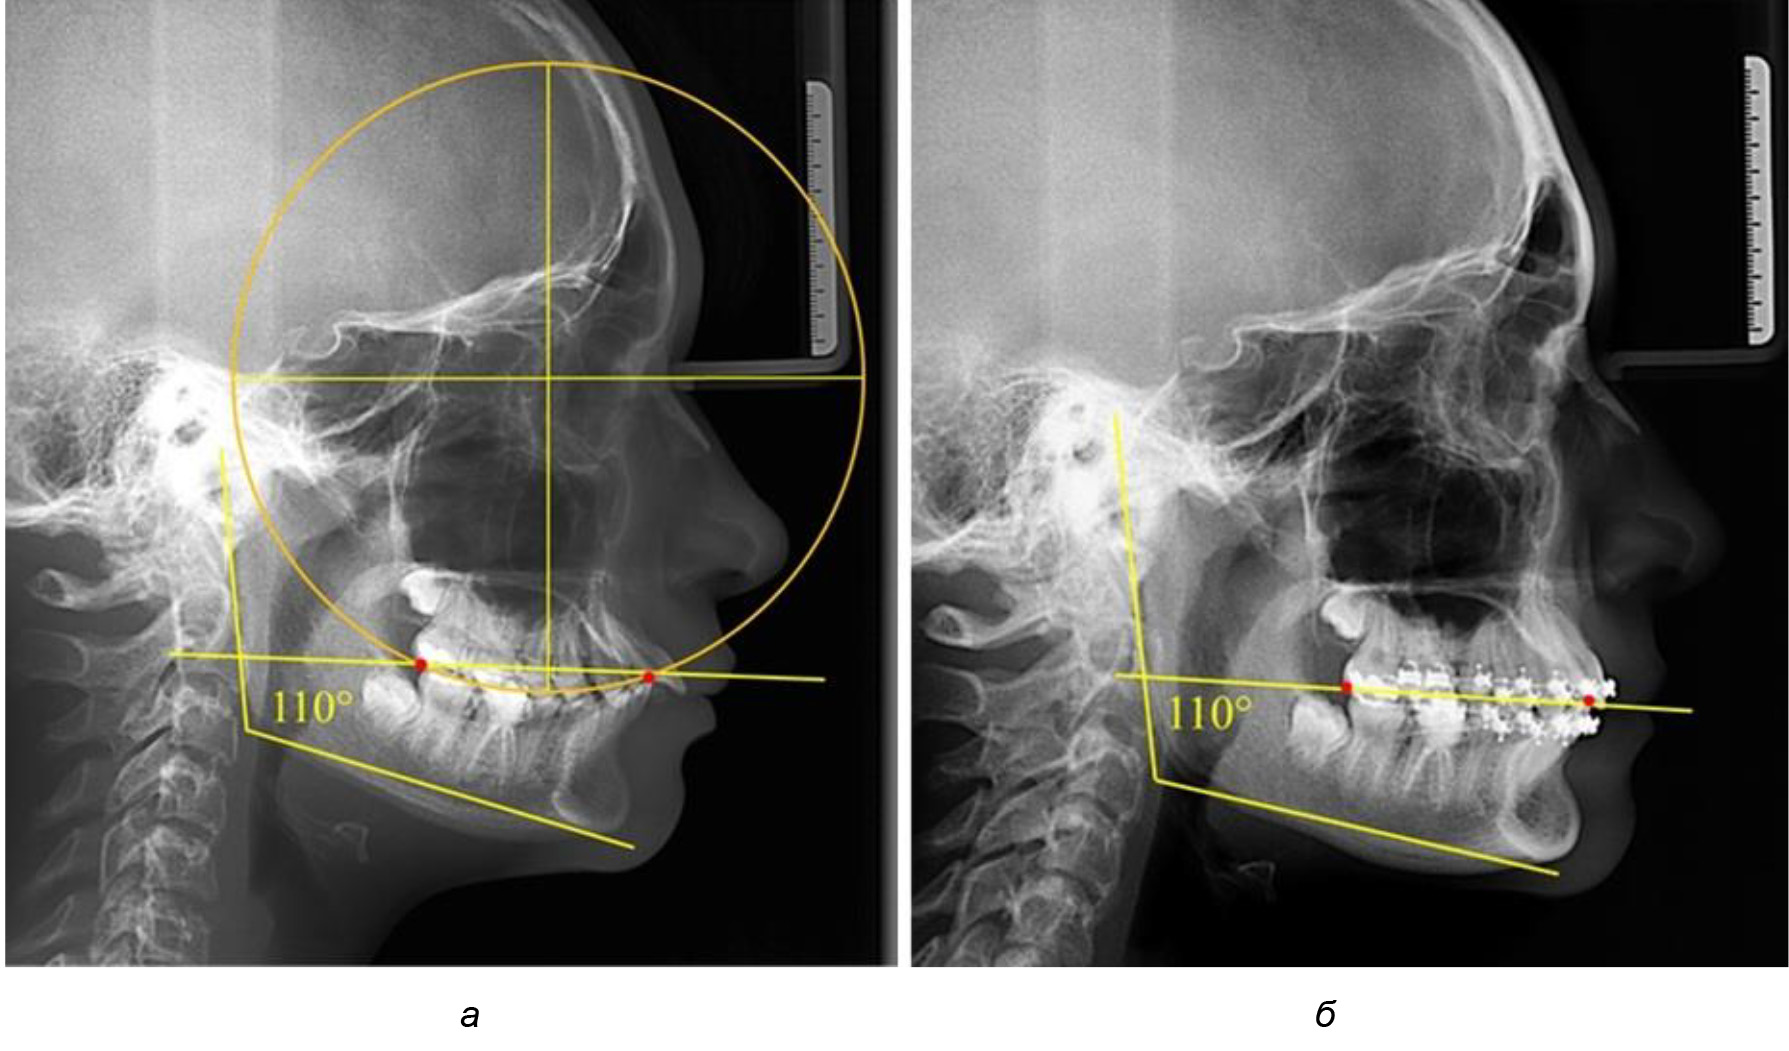

Рис. 1. Метод определения кривой Spee на ТРГ (а) и на ОПТГ (б)

Рис. 5. Особенности ТРГ при патологической кривой Spee до лечения (а) и после лечения (б) техникой «прямой» дуги

Рис. 6. Особенности ТРГ при оптимальной кривой Spee до лечения (а) и после лечения (б) техникой «прямой» дуги